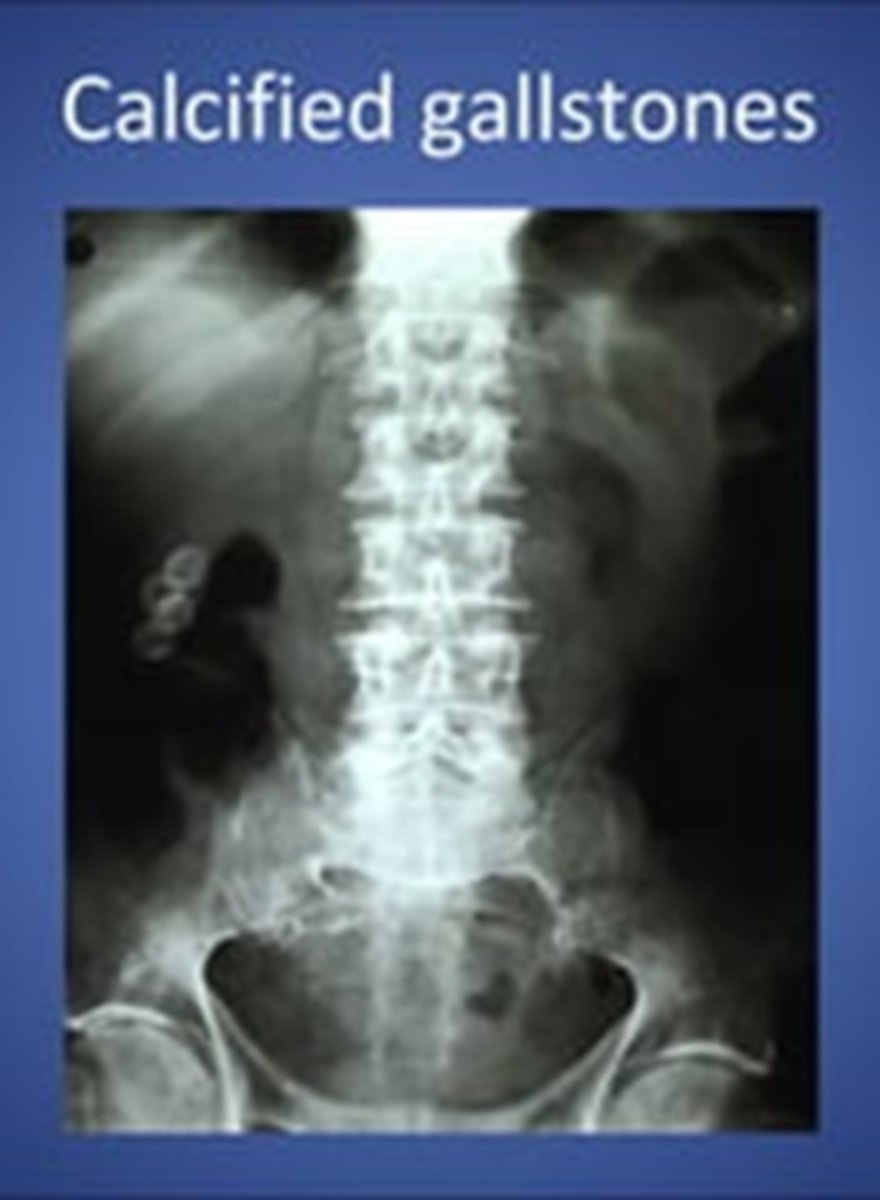

etiology of most calcifications can be determined by evaluatin

anatomic location, pattern of calcification